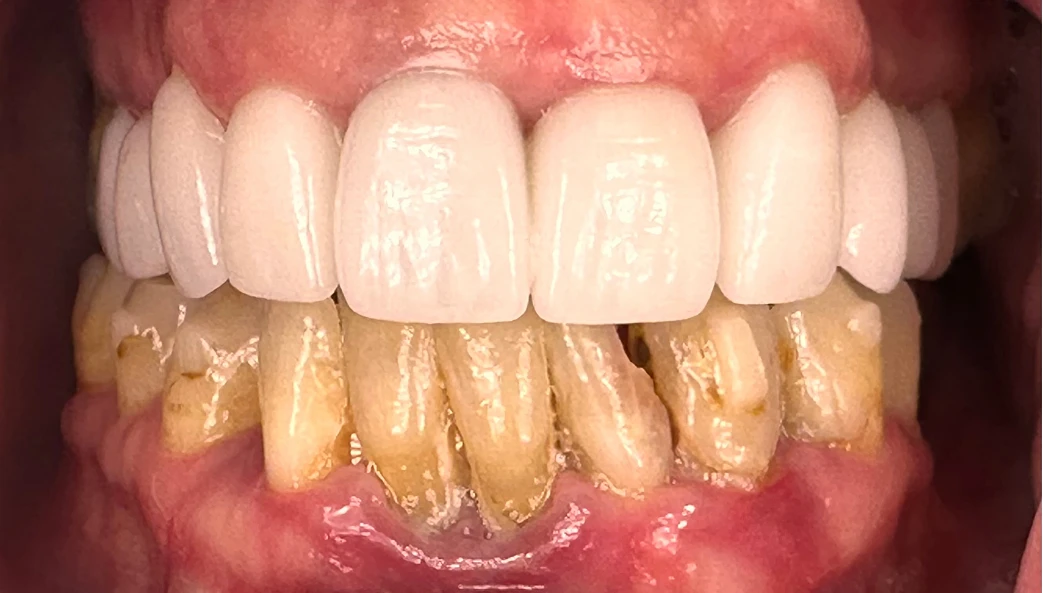

Our patient, a 41-year-old female from Portland, came to us in 2023 seeking help for what she described as "ugly teeth that don't work." She was unhappy with the dark, yellow discoloration and severe crowding. Smiling was something she avoided. Eating was difficult. Her lower teeth were painful and mobile, bleeding easily when brushing or chewing. Dental anxiety and financial concerns prevented her from moving forward at first — but a year later, motivated and ready, she returned determined to change her life.

On examination:

Upper Arch

- Teeth were discolored, worn, crowded and decayed.

- Arch form was narrow with a missing upper lateral incisor.

- Bone support was better than the lower arch, making these teeth restorable.

Lower Arch

- Advanced periodontal disease with significant bone loss.

- Multiple teeth were mobile and symptomatic.

- Two impacted retained teeth added complexity.

- Only a small number of posterior teeth were technically restorable — not ideal for long-term function.